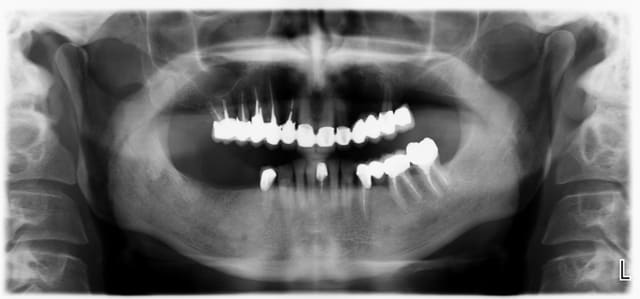

Allez, cas fini cette semaine, je vous le présente tel qu'il est arrivé.

La pano est dégueulasse, à l'époque je n'avais pas encore la mienne, merci les radiologues.

Pour compléter donc:

-pas de lésions apicales visibles, les dents non dévitalisées répondent au test de vitalité.

-Pas de poches supérieures à 6 mm.

-Pas de photo du visage pré-traitement, le patient ne sourie pas, probablement complexé, et je n'ai pas voulu en rajouter.

-Brossage moyen, ok dès la première séance après enseignement de l'hygiène.

-La 23 est foutue, cariée jusqu'au trognon.

La pano est vraiment dégueu mais traitement idéal pour moi : extraction de tout en haut sauf 12 11 21 22 (13 ? on voit rien) (emax sur dent vivante) et implanto après traitement paro.

Le bas est plus sujet à discussion, mais extraire 36 37 (paro + égressées), composites ou couronnes selon l'atteinte carieuse, et implanto après paro pour les dents manquantes.

En l'occurence, même si pas mal de solutions étaient valables, on en a choisi une plus proche de celle de Thomas Crown. (en vrai, c'est un peu moins moche que sur la pano.)

Pour compléter également, pas de mobilités, hormis 24/25. Pas de lésions furcatoires.

La 16 a été amputée de sa racine MV, mais le patient ne se souvient plus quand.

Patient relativement jeune (entre 50 et 60 ans)